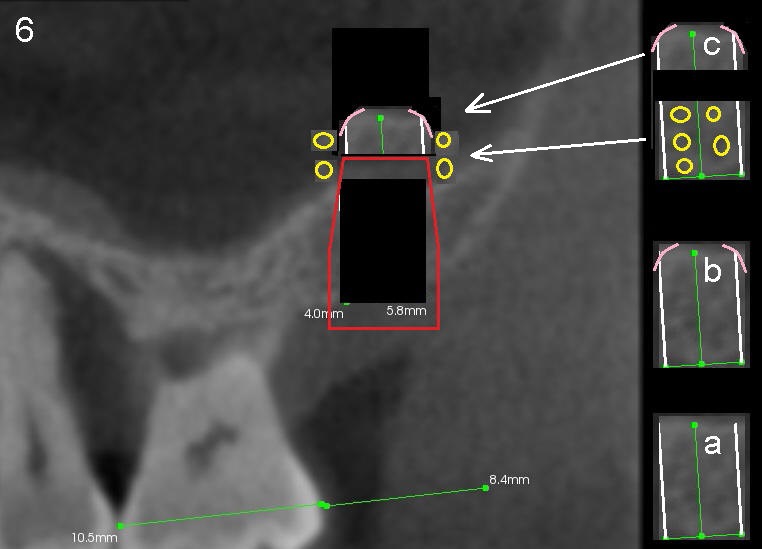

If the bone core comes out with the trephine bur (Fig.6a), the top corner will be trimmed (Fig.6b pink curved lines) so that it will not tear the sinus membrane when it returns as will be mentioned below. The bone core is to be sectioned as shown in Fig.6c. The top portion will be placed above the implant, while the lower portion will be ground into small pieces (yellow circles) with a bone mill and placed lateral (circumferentially) to the implant.